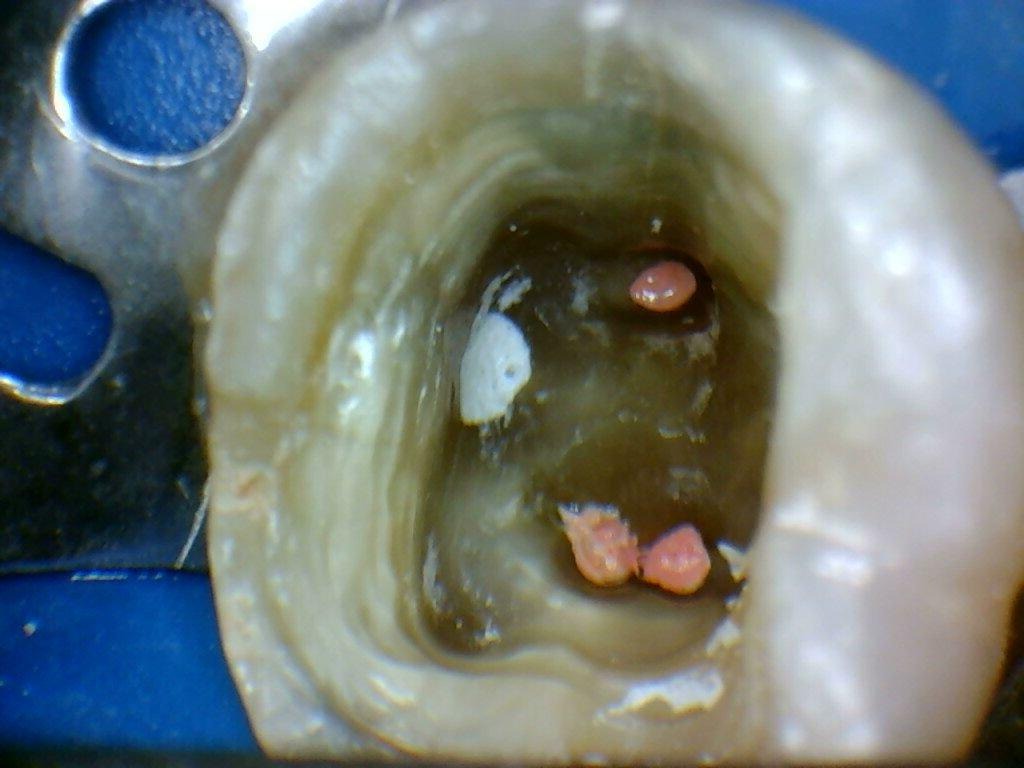

A localização dos condutos radiculares foi realizada com o auxílio de equipamento ultrassônico, sob supervisão de profissional especializado, permitindo precisão e segurança durante o procedimento. Após a localização, aplicou-se uma barreira gengival apenas na área da perfuração, permitindo o uso controlado de irrigantes potencialmente irritantes sem comprometer a região, o que possibilitou a continuidade do tratamento de forma segura.

Localização dos conduções e canais instrumentados